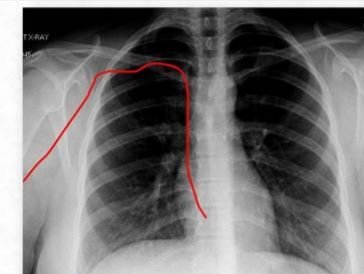

PICC置入术是指经外周静脉(贵要静脉、肘正中静脉、头静脉、肱静脉)进行穿刺插管,末端位于上腔静脉的导管。该技术具有操作简单、穿刺部位多、耐高渗、易护理、保留时间长等特点。适用于肿瘤化疗、中长期静脉输液、需长期静脉营养、新生儿、早产儿、缺乏外周静脉通道、输注刺激性和腐蚀性药物、家庭病床的患者等。能大大减少反复静脉穿刺给患者带来的痛苦,真正实现"无痛输液"。